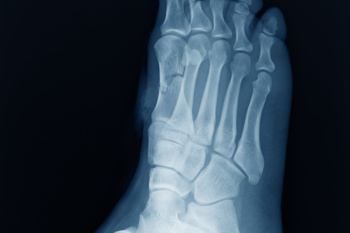

Pain in the front of the ankle can develop when bone spurs or inflamed soft tissue create pressure where the tibia and talus bones meet. This leads to a pinching feeling as the ankle bends upward while walking or climbing. Such pressure often increases after repeated sprains, frequent forward-leaning movements, or long-term strain from activities like soccer or dancing. People may notice discomfort when walking uphill, rising from a squat, or moving the ankle toward the shin. An X-ray can show bony growths that limit motion, while an MRI scan can reveal swelling or scarring in the front of the joint. A podiatrist can evaluate ankle alignment, review imaging, provide shoe inserts for added support, and discuss surgery when needed to remove spurs and improve mobility. If you have pain in the front of your ankle, it is suggested that you schedule an appointment with a podiatrist for a full exam and options for treatment.

Diagnosis

Due to the wide variety of potential causes of ankle pain, podiatrists will utilize a number of different methods to properly diagnose ankle pain. This can include asking for personal and family medical histories and of any recent injuries. Further diagnosis may include sensation tests, a physical examination, and potentially x-rays or other imaging tests.